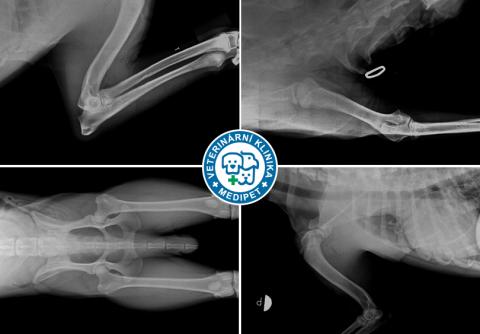

Certifikované posuzování dědičných ortopedických vad u psů na Veterinární klinice Medipet

Složením specializačních zkoušek je MVDr. Jiří Jahoda od r. 2003 posuzovatelem dědičných ortopedických vad u psů. Jedná se o posuzování dysplazie kyčelního kloubu (DKK), dysplazie loketního kloubu (DLK), osteochondrózy (OCD), spondylózy a luxace čéšky (PL). Kromě luxace čéšky, která se posuzuje klinicky, je prováděno posuzování RTG snímků.